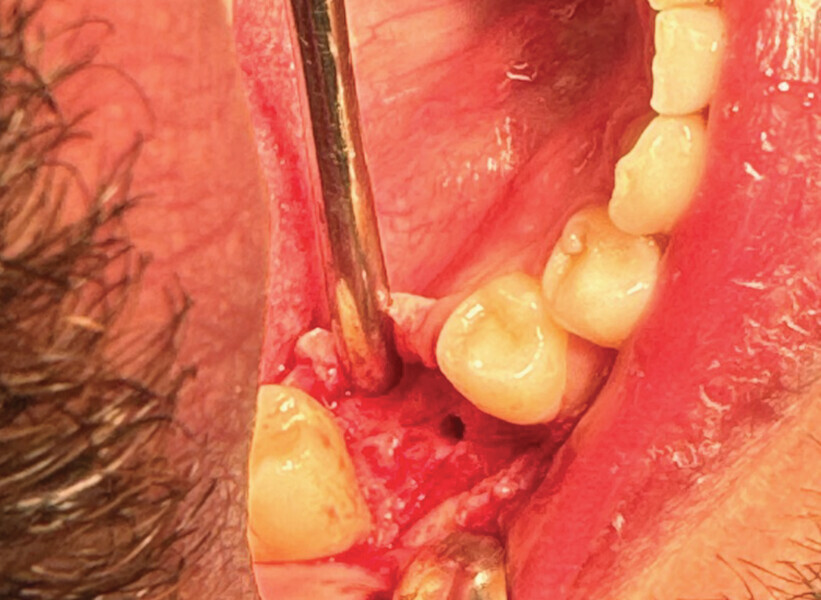

Fig. 1

Le patient, âgé de 27 ans, présentait un kyste apical ainsi qu’une atteinte de la furcation de la 46 ne nous permettant pas le retraitement et l’exérèse kystique. La décision de l’avulsion a donc été prise, en vue de la pose d’un implant (Fig. 1).

L’avulsion a été faite après anesthésie avec une ampoule de SEPANEST 40 mg adrénaline à 1/200000e. L’acte chirurgical est réalisé de manière la plus atraumatique possible, exérèse et curetage du kyste apical, nettoyage de l’alvéole. Dans ce cas précis, nous n’avons rien mis dans l’alvéole car les quatre murs alvéolaires ont pu être conservés. Un léger décollement des muqueuses vestibulaires et linguales a été nécessaire pour la mise en place de la membrane R.T.R.+.* La structure de cette membrane est faite pour être positionnée dans un sens précis, la surface lisse est toujours positionnée vers l’extérieur et la face rugueuse en regard de l’os.